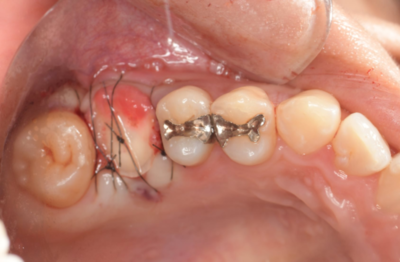

抜歯1ヶ月後

移植手術後

右上6抜歯1ヶ月後、移植手術を行った。

右下8を抜歯し右上6部に移植、縫合糸で固定した。

移植手術後、治癒に異常を認めなかったため、移植2週間後に根管治療を行った。